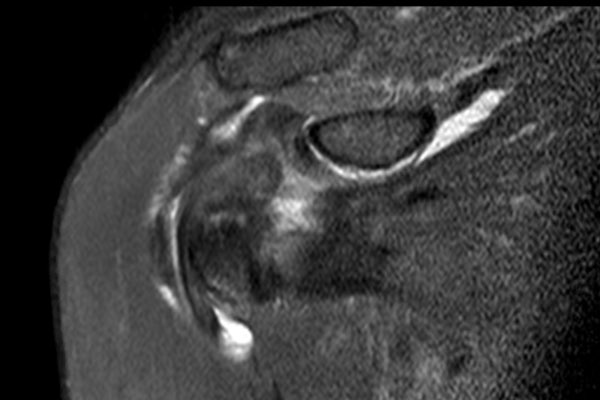

Hình ảnh

Chuỗi xung T2W xóa mỡ mặt phẳng axial và chuỗi xung PD mặt phẳng sagittal chếch.

Có hình ảnh rách không hoàn toàn gân dưới vai kết hợp với phù nề do gãy mấu động nhỏ (lesser tubercle).